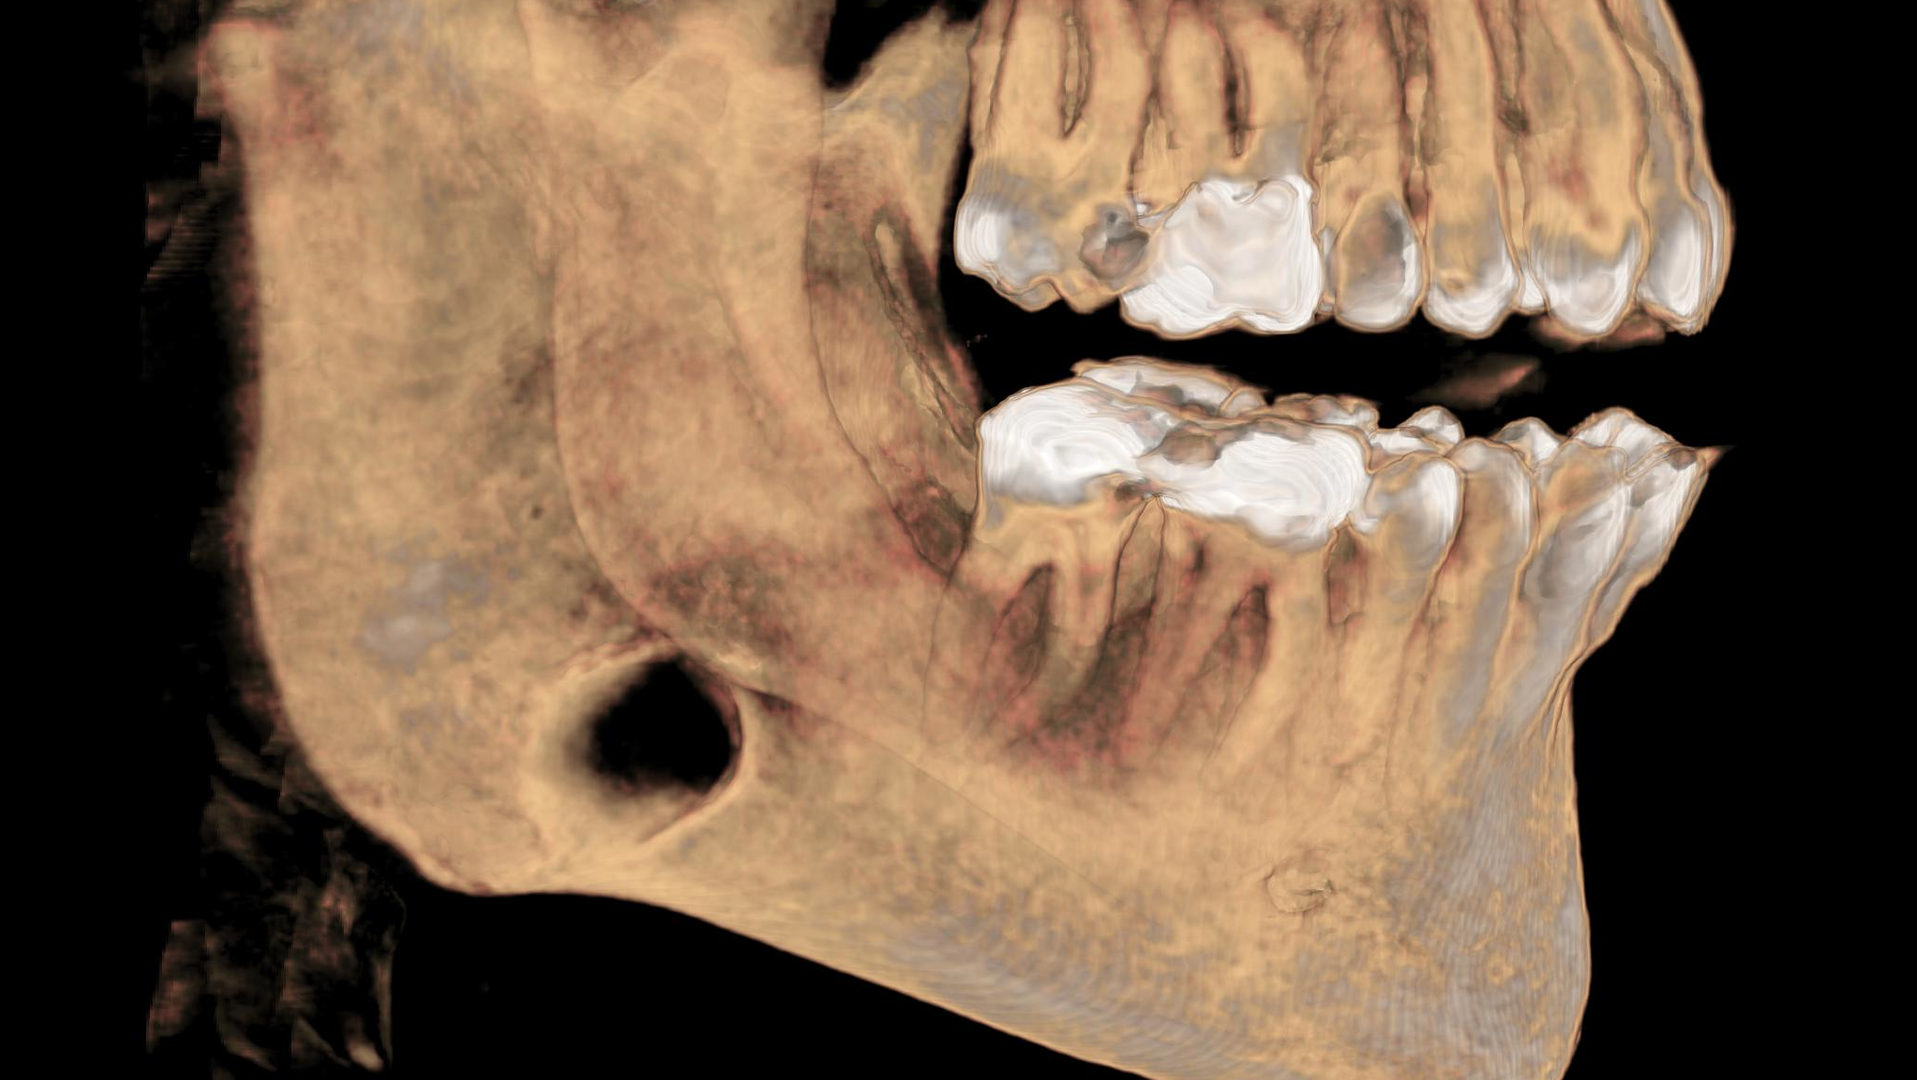

As part of our intake process to make a sleep mandibular advancement device, we take a cone beam image (figures 1–4). This way we can evaluate sinuses, septum, turbinates, teeth, and jaws.

Upon examination, it was noted that a dark, radiolucent lesion was present on the lower right jaw, anterior to the angle of the mandible. The patient didn’t have any pain, symptoms, or knowledge of the lesion. It was not palpable. He reported that he had his third molars removed in his twenties with no complications.

The Stafne defect is code for a depression in the bone, a concavity, due to the submandibular gland. In addition, it can’t be qualified as a cyst because there is no epithelial lining or fluid content. It does usually occur more in men as well.1 There is no treatment necessary; it’s something we can just monitor.